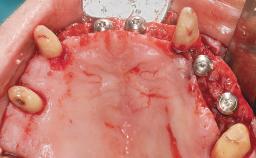

Conventional Loading of Eight Implants in the Maxilla and Final Restoration with a Full-Arch Gold-Ceramic FDP

A 35-year-old Caucasian female presenting with advanced periodontal disease involving both the maxillary and the mandibular dentition was referred for evaluation. The patient, a non-smoker in good general health, requested treatment for recurrent periodontal abscesses, tooth mobility, and discomfort during chewing, as well as restoration of her missing teeth with a fixed prosthesis to improve mastication and esthetics. All residual maxillary teeth exhibited plaque deposits, deep pockets, bleeding on probing, and class III mobility and were evaluated as hopeless. All residual mandibular teeth except tooth 37 could be maintained after periodontal therapy.

# of Implants 8

Defining Characteristics Fully edentulous upper jaw to be rehabilitated with four or more implants